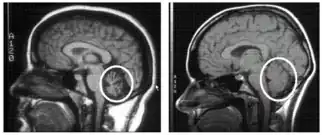

To select an appropriate and accurate diagnostic test for cerebellar degeneration, it is crucial that a range of factors specific to each patient are taken into consideration. These include; the patient's age, acuity of their signs and symptoms, associated neurological conditions, and family history of hereditary forms of cerebellar degeneration.[3] A diagnosis for cerebellar degeneration is regarded after any of the aforementioned signs and symptoms surface. For genetically classified forms of cerebellar degeneration, genetic testing can be carried out in order to confirm or deny the diagnosis, where this form of testing is only possible if the gene responsible for the cause of the condition is recognised.[24] In saying this, for most conditions the genetic cause of cerebellar degeneration is unidentified, hence these patients cannot proceed with genetic testing.[1] In cases where cerebellar degeneration is acquired, a diagnosis can be established using imaging methods such as computerised tomography (CT scans) and magnetic resonance imaging (MRI), necessary to detect brain abnormalities in patients with cerebellar degeneration.[25]